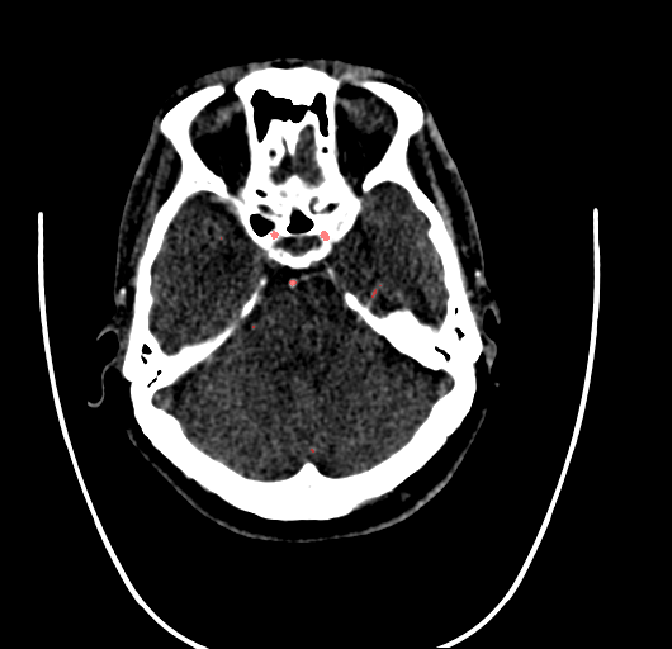

After fine-tuning, the two pre-train conditions appear to have little or no difference in terms of qualitative performance at the vessel segmentation task. However, when compared to the models trained only on real data, there are noticeable differences. Throughout Figures 4.3-4.9, the model pre-trained on scans with original CT noise is to be taken as representative of segmentation performed by the Perlin noise pre-training condition. Images showing the hand-labeled ground truth, as well as the unlabeled slice, are presented for comparison.

Figure 4.4: Segmentations on regions near internal carotid arteries. Unaltered image (left). No pretrain model (mid-left). Fine-tuned model (mid-right). Hand-labeled ground truth (right).

In the other hand, it should be noted that fine-tuned models suffered from false positives more often than models with no pre-training. The fine-tuned models appeared to occasionally segment regions near the skull, which although similar in intensity to vessels, had no resemblance in terms of shape. Examples of this are seen in Figure 4.4 near the occipital bone and near the right temporal bone. Examples of oversegmentation were observed to happen commonly around the internal carotid arteries. This is likely due to the amount of contact surface between the artery and the surrounding bone. There was also a tendency for all model conditions to segment bone regions that were similar in shape to large vessels (Figures 4.3 and 4.4). Bone structures in such regions have similar pixel intensities to the arteries transporting contrast material, which could explain the source of confusion for a model.